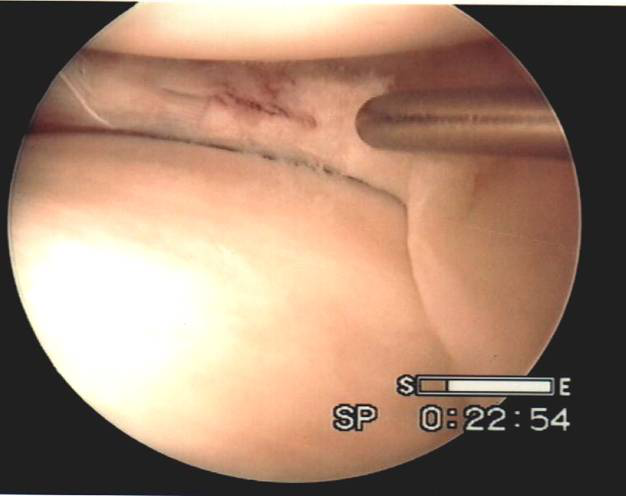

盤狀半月板的切除-鏡下解剖

v盤狀是畫盤的盤,象蠶豆,不是園盤的盤。由于緊挨者ACL,前角處有梨把凹陷與ACL緊密相貼。外側(cè)有腘肌腱和滑膜緣關(guān)節(jié)囊,前后角都基本在中線前后1/3處。

v所以要以ACL、腘肌腱、外緣關(guān)節(jié)囊為解剖標志,隔開ACL、腘肌腱,而外緣留多少無所謂,注意ACL、腘肌腱的損傷。外緣用刨刀再處理。

v通過改變器械進入的角度、器械本身的彎曲來完成,直剪用處很大,結(jié)合左右彎藍鉗或推鉤刀切除

盤狀半月板的切除順序

v器械在同側(cè)、對側(cè)操作無所謂,都可以切除,根據(jù)優(yōu)勢手

v先切斷前角(下垂位)(對側(cè)或同側(cè))(鉤刀或推刀),沿著外緣咬到腘肌腱處(下垂內(nèi)推下拉)(最好在同側(cè),對側(cè)先咬也行,再換成同側(cè)咬體部外緣后部)

v再建一入路牽拉下,倒著切斷后角匯合(下垂內(nèi)推下拉或大4)(操作最好對側(cè),也可在同側(cè))

v亦可兩入路,一直咬到后角斷開或后角倒咬匯合。

v旋著取出